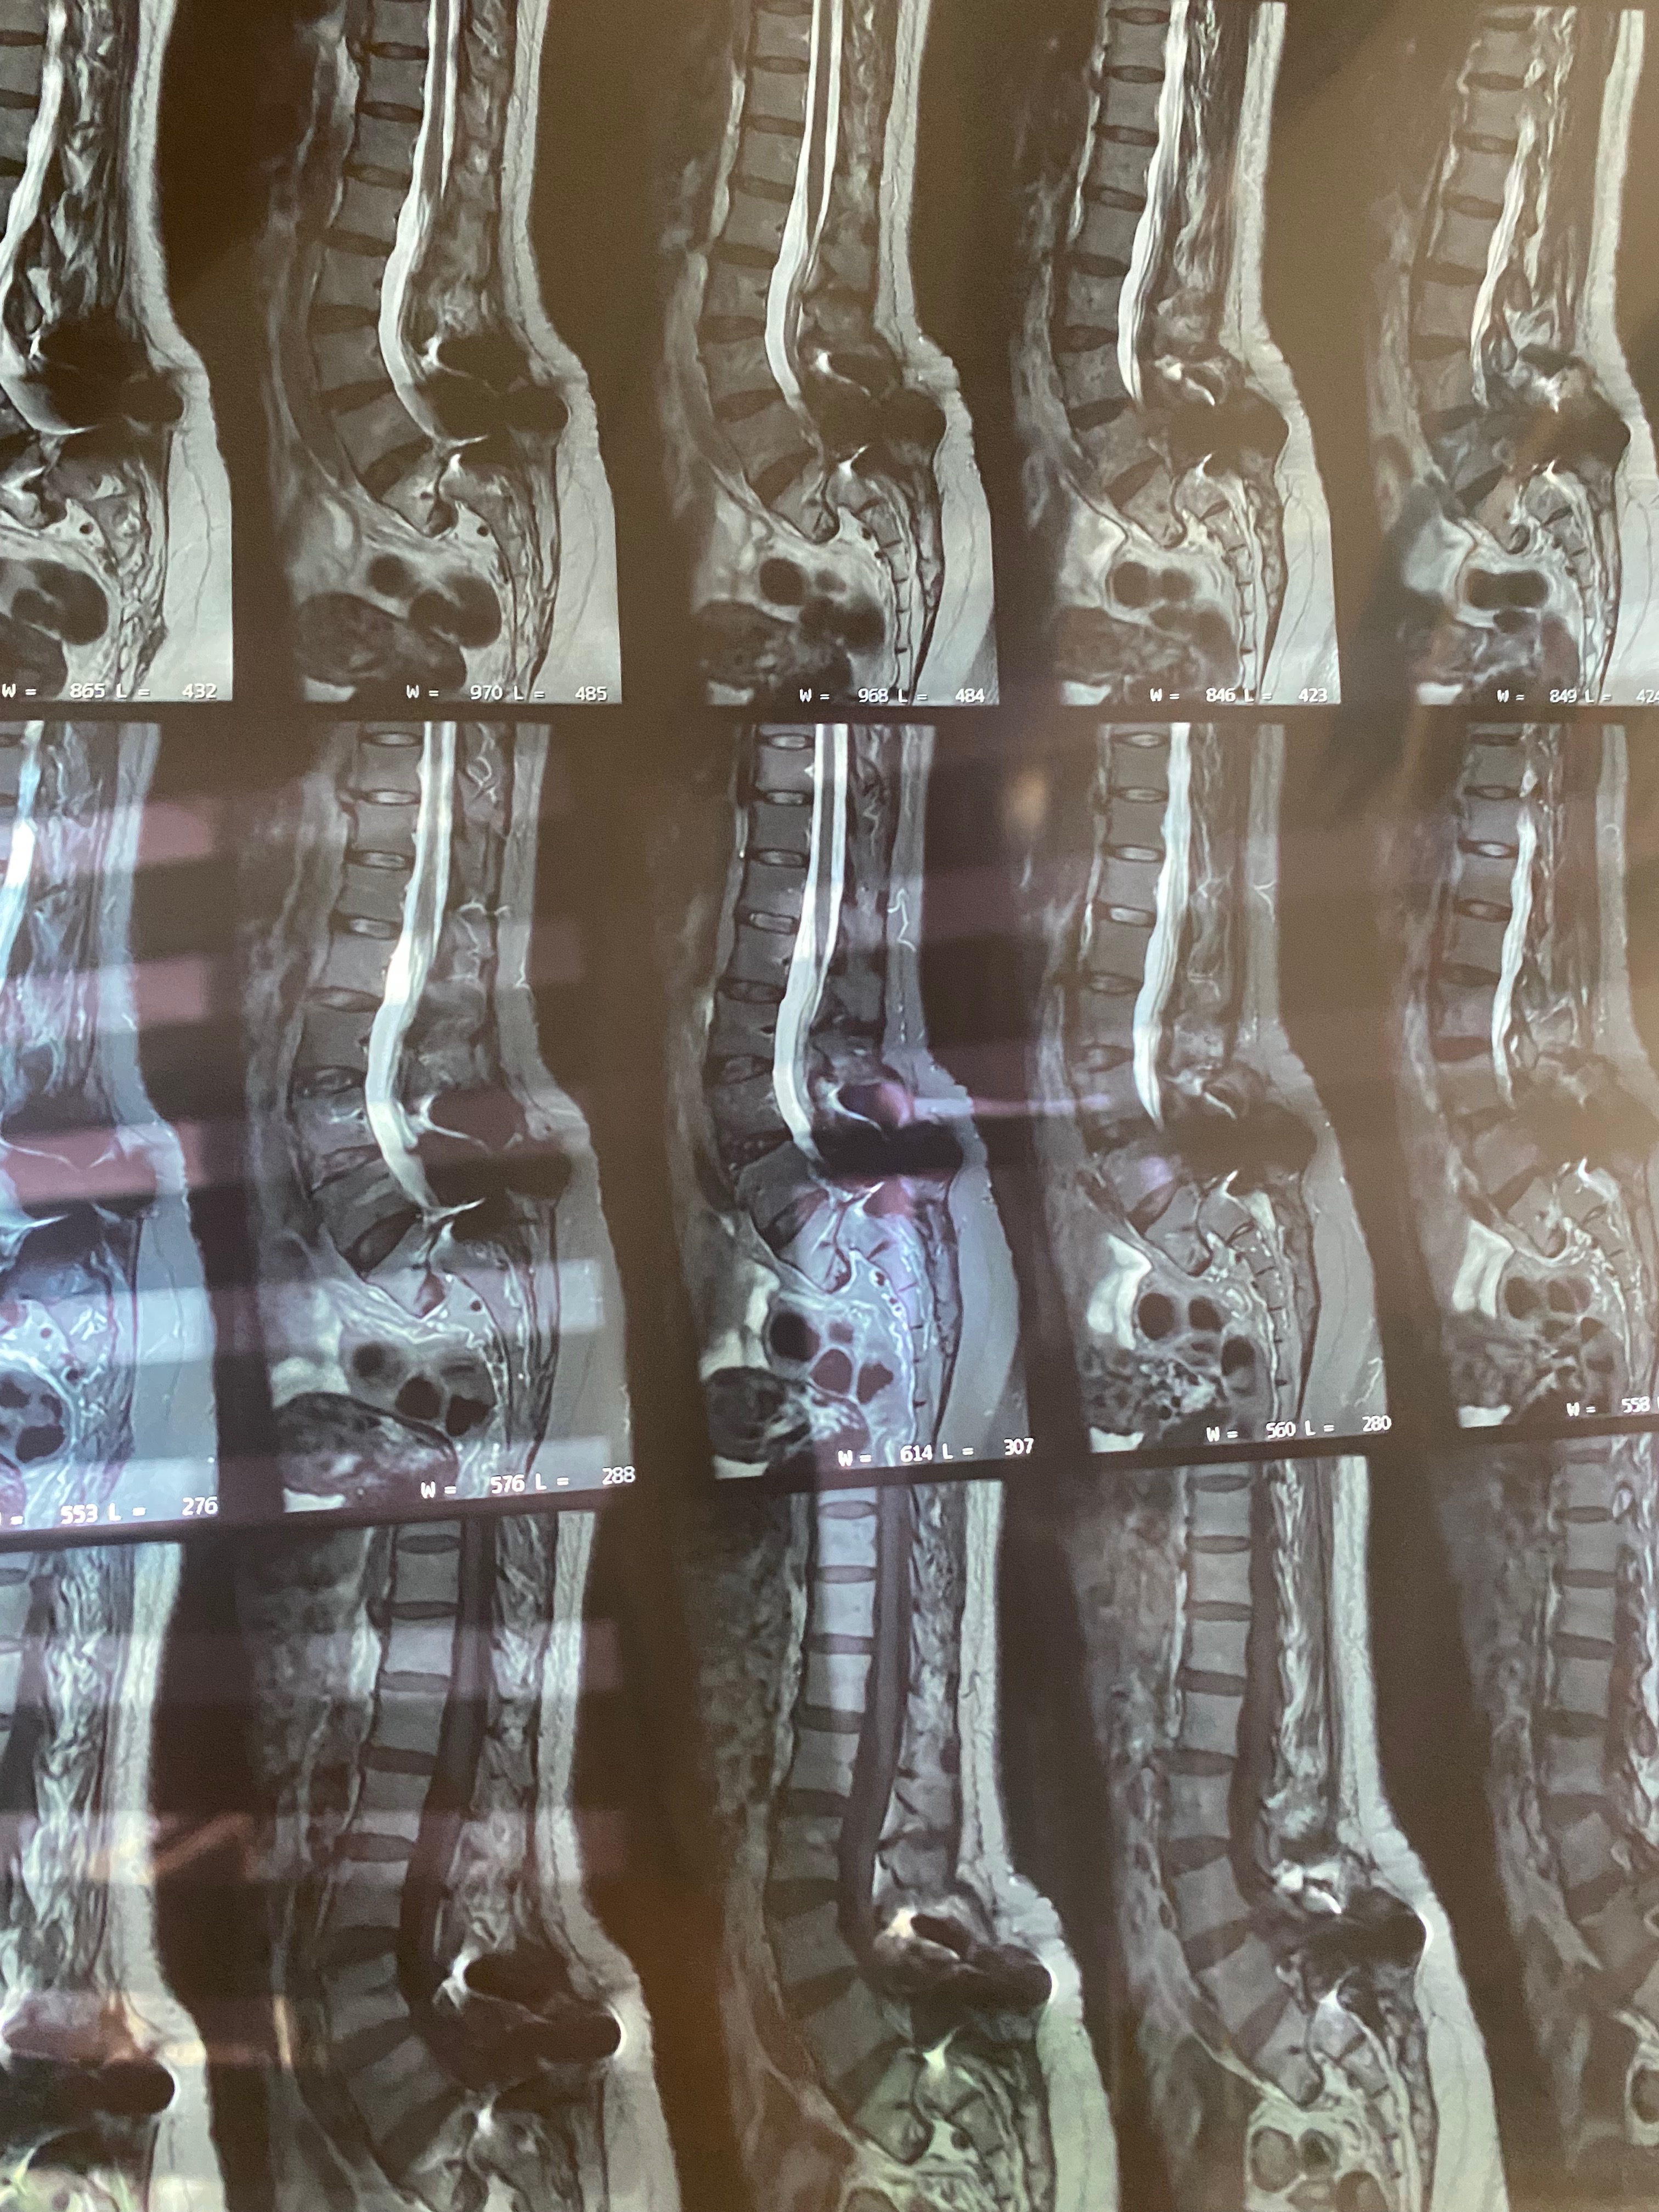

Hace 28 años, mi mamá fue operada de la columna y le colocaron prótesis de metal que, con el paso del tiempo, dejaron de ser funcionales. En los últimos meses, su condición ha empeorado: presenta dolor constante, adormecimiento en las piernas, mareos y una dificultad cada vez mayor para caminar, sentarse y descansar.

Buscamos atención en el sistema de salud público, pero nos informaron que no cuentan con el material necesario ni realizan este tipo de cirugía. Los médicos fueron claros: la intervención no es opcional. Si no se realiza a tiempo, mi mamá corre el riesgo de perder la capacidad de caminar.